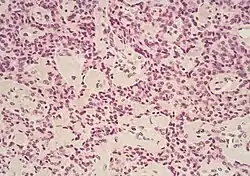

Cancer type | Relative incidence[11] | Microscopy findings[11] | Micrograph | Immunohistochemistry markers[11] | Genetic alterations[11] |

Pancreatic neuroendocrine tumor | 5% | Multiple nests of tumor cells | ![]() |

||